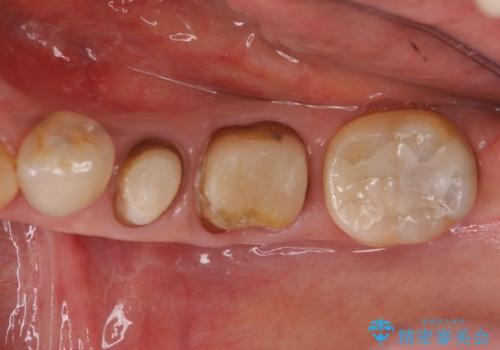

- 左下の銀歯を白くしたいと来院。

左下5番は根管治療のやりなおし、左下6番は上物(クラウン)のやり替えのみを行いました。

左下7番はアマルガムが入っていたため、ご希望によりセラミックインレーで治療を行っています。